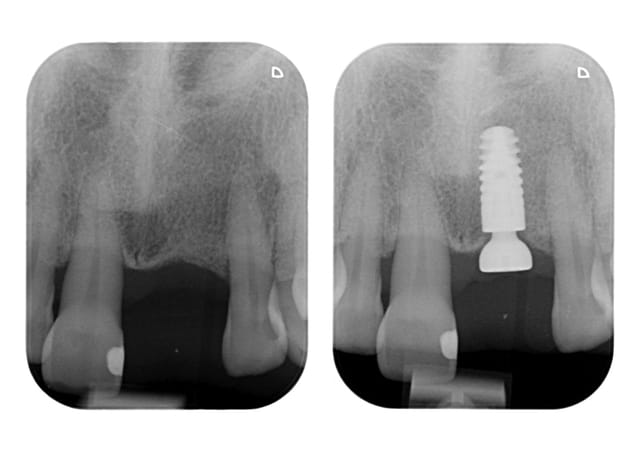

"a pas peur" la 11 ne résistera pas longtemps implant d'entrée de jeux aurait été le mieux il me semble, c'est sur quelque fois le gout bloque le patient mais au vue de la radio chaud chaud les marrons , bon c'est noël c’était facile!!!!!!!!!

Elle est en pleine forme cette 11, pas de mobilité un bel os, je vais essayer de la garder, sinon si ça marche pas, ben on l’enlèvera, en attendant je vais lui laisser sa chance.

Sauf votre respect, il n'y a actuellement aucune papille en mésial de la 11.

Cette dent est parodontalement parlant plutôt môche.

Avec une couronne sur l'implant 21 et une dent 11 tel-quel, ça sera pas beau

L'implant choisi est très bien, connection sous crestal stable.

Il y a amplement d'espace inter-implants pour placer un autre Ankylos et avoir au final quelque chose de bien plus stable que cette dent 11.